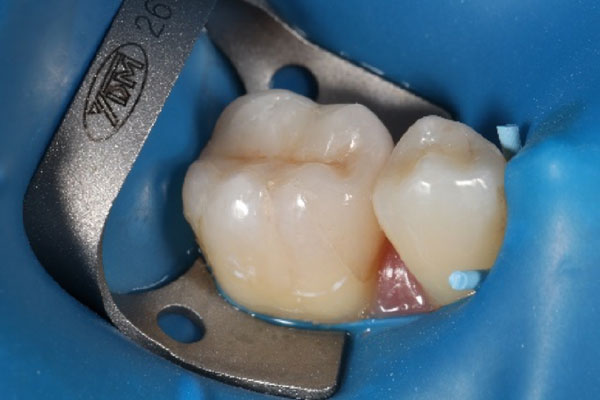

(1)ラバーダム防湿

お口の中には唾液中に様々な細菌が存在しています。根管内部に唾液が入り込めば細菌が感染してしまいます。そのために根管治療を成功させるためには必須のものがラバーダムです。

これは薄いゴム製のマスクのようなもので、治療する歯以外を薄いゴム製シートで覆いかぶせることで、治療する歯に唾液が入り込むことを防ぎます。手術時に治療中の場所以外を覆ってしまうのと同じ考え方です。さらには喉の奥に薬液が垂れるのも防ぎます。

根管治療でラバーダム防湿を行うことは欧米では必須の処置となりますが、日本で実施している医院は全国でも数パーセントしかないと言われています。当院で行う根管治療はラバーダム防湿をしっかり実施しております。

患者さんのお口にゴムのマスクを装着します。

実際にお口を覗いてみると…